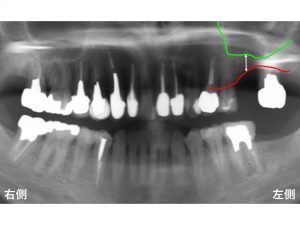

わかりやすいように骨吸収の状態を線でかいて見ます。

以下の青線が骨吸収する前の元々の骨の位置です。

現在の骨吸収した状態が以下の赤線です。

そして緑線が上顎洞の一番下の部分です。

この3つの線を組み合わせたのが以下です。